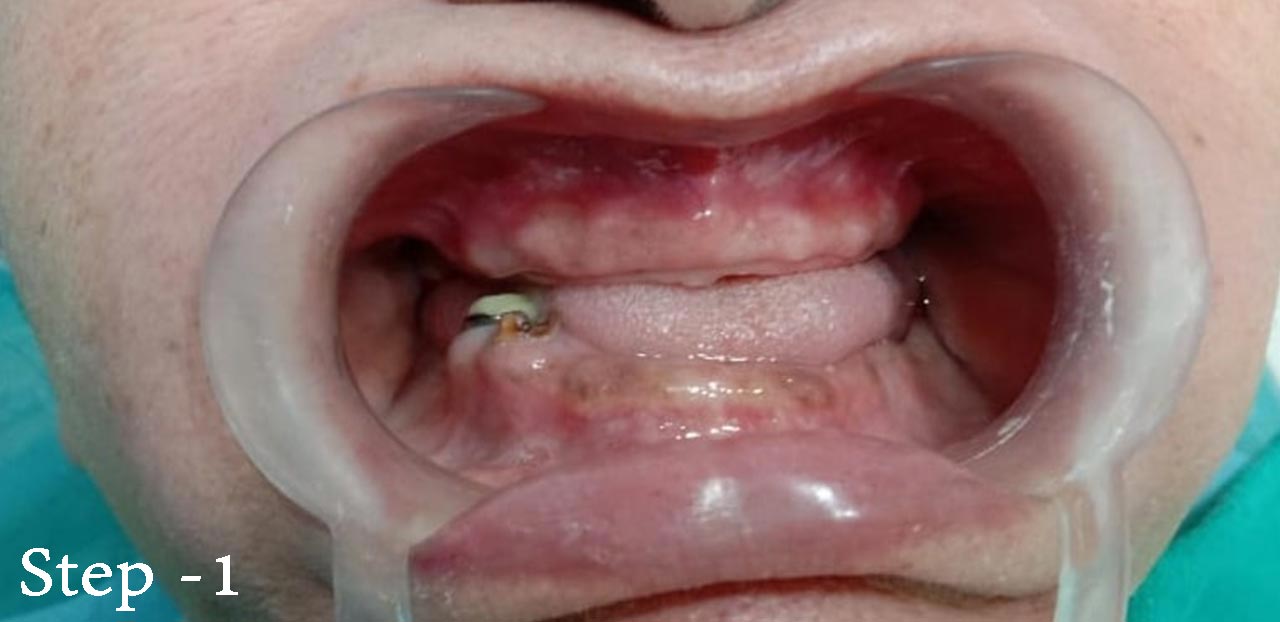

62 yrs female patient presented at the clinic suffering from an inability to feed herself for the last few years and lack of confidence in social situations due to the severe caries in front teeth. Additionally she was suffering from recurrent abscess formation. The patient had visited other clinic,all of which had done failed restoration and inappropriate RCT and restoration. She was looking for fixed and esthetic teeth with strong and functional. The patient medical history was clear. A clinical and radiological examination was carried out to assess the PT's suitability for implant placement. On the upper jaw she decayed and retained roots in the front region.In order to provide the pt with an accurate diagnosis and to evaluate bone level and quality for potential implant placement,a 3d cbct Scan was performed. The quality of the alveolar bone seemed adequate for implants placement and no extra bone graft required for implant surgery. Treatment planing--- The plan was to remove all the decayed front teeth and placement of six implants,3 side by side and then followed by fabrication of screw retained zirconia bridge after healing period of 4 months

fig 1 - Baseline photograph when patient presented herself in the clinic,all front teeth decayed and damaged